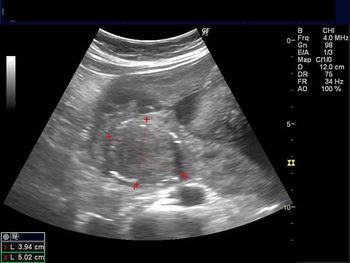

This middle-aged woman has a history of dysmenorrhea. What is your diagnosis based on these images?